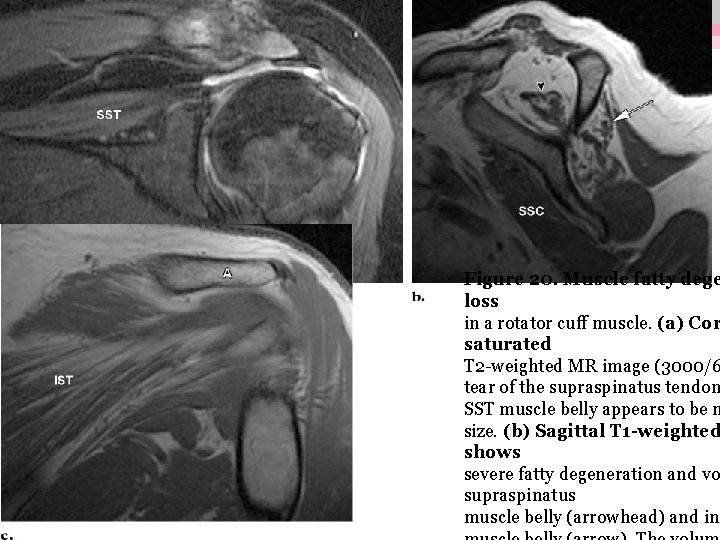

Conséquence musculaire de la rupture: • Dégénérescence graisseuse: - d’autant plus marquée que la rupture est étendue ou ancienne - survient au minimum 6 semaines après la rupture - muscle ss-épineux++(même si tendon non rompu/ rupture étendue sus-épineux et ss-scap) - Importante à considérer car conditionne les résultats fonctionnels post-opératoires

- 5 stades: classification de Goutallier ▪ stade 0 : pas de graisse ▪ stade 1 : quelques traces de graisse ▪ stade 2 : moins de graisse que de muscle ▪ stade 3 : autant de graisse que de muscle ▪ stade 4 : plus de graisse que de muscle

Figure 20. Muscle fatty dege loss in a rotator cuff muscle. (a) Cor saturated T 2 -weighted MR image (3000/6 tear of the supraspinatus tendon SST muscle belly appears to be m size. (b) Sagittal T 1 -weighted shows severe fatty degeneration and vo supraspinatus muscle belly (arrowhead) and inf